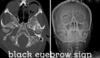

What are the DVLA driving rules for the following:

- Visual Acuity

- Visual Fields

- Diplopia

Visual Acuity: must be able to read number plate at 20m (6/10 on Snellen)

Visual Fields: If binocular vision >120 degrees fields, if monocular vision need full visual field

If diabetic retinopathy need yearly visual field tests

Diplopia: Not allowed unless mild or eye patch correctable